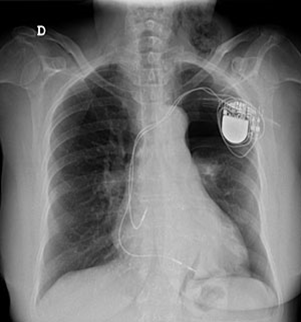

¿Cuanto dura un marcapasos?: Los marcapasos implantados actuales duran generalmente entre ocho y diez años (dependiendo del tipo de condición cardíaca) y, en la mayoría de los casos, permiten que la persona lleve una

vida normal. Además, con los avances en los sistemas de circuitos de los marcapasos, se ha reducido el riesgo de interferencias provenientes de ciertos aparatos, como por ejemplo los microondas, que en el pasado podían alterar o afectar de alguna forma a los marcapasos.